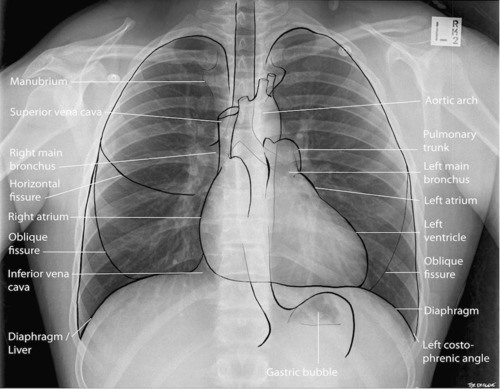

Lung Anatomy

Pulmonary Fissures

Lateral View

Can see b/l oblique fissures and horizontal fissure on the right.